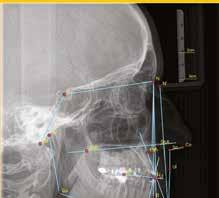

A CT metszetekben a 48-as gyökerei körbeölelik a canalis mandibularist, amelyet piros nyíllal jelöltünk a fotókon.

A fogak fejlődési üteme nagy szórást mutat, így mindenkinél egyéni az az életkor, amikor az optimális idősávban tudunk

operálni. A két legfontosabb tényező, amit sebészeti szempontból figyelembe kell venni, a gyökér helyzete a nervus alveolaris inferiorhoz képest, illetve a korona mandibula felszínéhez viszonyított pozíciója.

Általában a csíra növekedésével a gyökér egyre közelebb kerül az ideghez, közben a korona egyre jobban felemelkedik a csontfelszín irányába. Az idő előrehaladtával bekövetkező változások az első tényezőt tekintve folyamatosan veszélyesebbé, a másodikat számításba véve viszont folyamatosan könnyebbé teszik a fog eltávolítását. Ideális esetben, ezeket mérlegelve választunk időpontot. A túl későn elvégzett műtéteknél magasabb a kockázata a nervus alveolaris inferior sérülésének, a túl korai beavatkozások esetén viszont nagyon mélyről kell eltávolítani a fogat, így a feltárásához több csontot kell preparálni.

Saját gyermekeimnek már kb. 10 éves korukban készítettem OPT-ket a bölcsességfogak helyzetének ellenőrzése céljából. Mindkettejüknek 60-70°-os szögben mezioanguláltak a fogaik, tehát biztos, hogy nem fognak normál pozícióban az erupciós síkig emelkedni, ezért az eltávolításuk indokolt. Ezzel addig várok, amíg egyrészt a lehető legkisebb prepa-

rációval tudom felszabadítani a koronát, másrészt, hogy a gyökerek 1-2 mm-nél ne kerüljenek közelebb a canalishoz. A fejlődési ütemüket követve, előreláthatólag kb. 15-16 éves korukra érik el a fogaik ezt az állapotot.

Szeretnék mutatni néhány ábrát az egyik bonyolult esetről, a közelmúltból. A CT-n látszik, hogy a három gyökér teljesen „körbenőtte” az ideget. Van olyan frontális metszeti kép, ahol csak a gyökerek vannak a nervus körül, ezen a szakaszon egyáltalán nincs meg a csontos fala a canalisnak. Szeparációs technikával, viszonylag könnyen, minimális traumával, szövődménymentesen sikerült eltávolítani a fog minden részét. A várakozásnak megfelelően, a beteg nem számolt be paraesthesiáról.